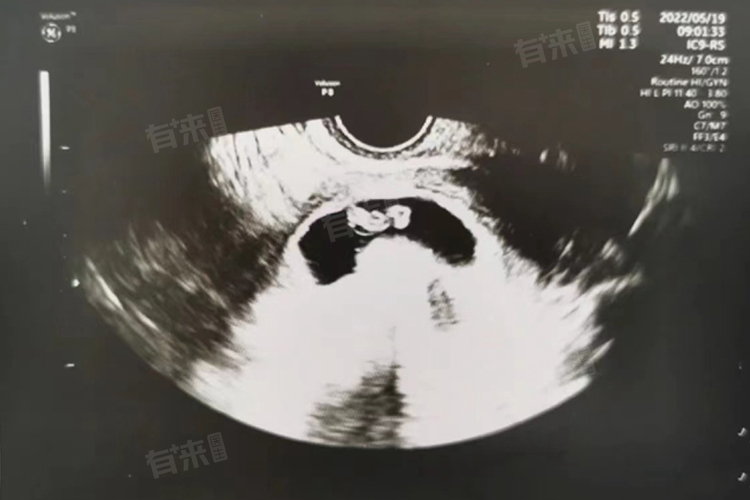

怀孕7周时,胎儿初具人形,头部明显,占身体比例较大,四肢已分化出幼芽,心脏开始有规律跳动。在妊娠第7周,胎儿整体长度为1-1.3厘米,重量仅约1克,虽如蓝莓般大小,却已完成从受精卵到初具人形的关键转变。此时胎儿头部显著,几乎占据身体一半长度,其内部神经管持续发育,未来将形成完整的脑和脊髓结构。

- 双眼开始以色素沉着的小凹形态出现,未来将逐步发育为视觉器官;鼻孔也已初步形成,为呼吸系统的发育奠定基础。四肢部位,手臂和腿部的幼芽已清晰可见,末端呈现桨状,未来会逐渐分化出手指和脚趾。尤为重要的是,心脏已发育成S形的管状结构,开始以每分钟约150次的频率有规律跳动,并通过原始血管网络输送血液,为全身发育提供营养支持。

7周胎儿处于器官分化和形成的关键时期,这一阶段胎儿对环境因素极为敏感,外界致畸因素如药物、辐射、病毒感染等,都可能干扰胎儿正常发育,导致器官发育异常。随着医学技术的发展,超声检查成为观察这一时期胎儿发育状况的重要手段,通过超声不仅能测量胎儿大小、评估发育进程,还能观察胎心搏动情况,为孕期保健提供重要依据。